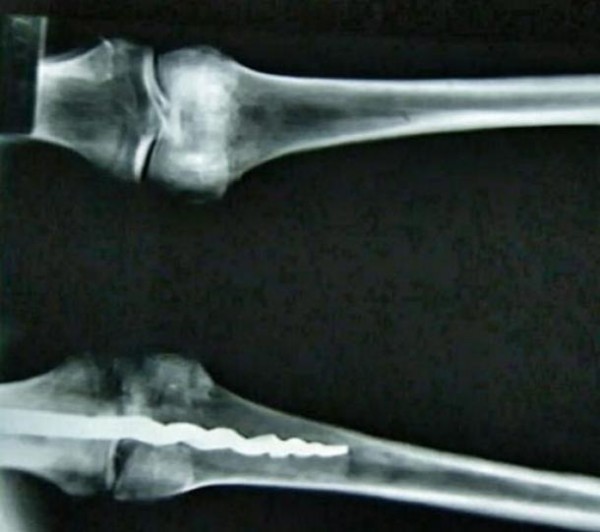

Μέσα στο αριστερό γόνατο βρέθηκε ένα μέταλλο 9 ιντσών, μια ορθοπεδική καρφίτσα για την συγκράτηση του οστού. Ήταν τοποθετημένη με τόσο προηγμένη μέθοδο για εκείνη την εποχή που αρχικά οι επιστήμονες δεν μπορούσαν να διακρίνουν αν είναι παρέμβαση της σύγχρονης εποχής.

Τον Αύγουστο του 1995, ο καθηγητής Γκρίγκς από το Πανεπιστήμιο της Γιούτας, μαζί με μια ομάδα εμπειρογνωμόνων που πέρασε από ακτίνες τις 6 μούμιες που φιλοξενούνται στο μουσείο έμειναν έκπληκτοι όταν ανακάλυψαν την ύπαρξη της ορθοπεδικής καρφίτσας και ανέφεραν χαρακτηριστικά ότι ακόμα μέσω των σύγχρονων μηχανημάτων ήταν αδύνατον να καταλάβουν από την πρώτη στιγμή αν τοποθετήθηκε στην σημερινή εποχή για να συγκρατήσει το οστό με το υπόλοιπο σώμα.

Προκειμένου να διερευνηθεί η φύση του εμφυτεύματος, μια ομάδα γιατρών και επιστημόνων με επικεφαλής τον Γκρίγκς διαπέρασαν προσεκτικά το οστό για να τοποθετήσουν μια ειδική μικροκάμερα για να εξετάσουν το μέταλλο και την παλαιότητα του.

Προηγμένες επιστημονικές μελέτες απέδειξαν ότι η επέμβαση πραγματοποιήθηκε πριν από 2.600 χρόνια. Όπως δήλωσε ο επικεφαλής της ομάδας:

Αυτό που μας εξέπληξε περισσότερο ήταν ότι εκείνη την εποχή βρέθηκε τρόπος να κατασκευαστεί με σχεδόν με βιομηχανικές αρχές αυτό το εμφύτευμα. Το τελείωμα του μοιάζει με τιρμπουσόν, το άλλο άκρο του έχει τρεις φλάντζες που εμποδίζουν την περιστροφή του εμφυτεύματος μέσα στο οστό.

Παρακολουθείστε την ερασιτεχνική λήψη μέσα από το μουσείο που δείχνει με κάθε λεπτομέρεια την μούμια του ιερέα Usermontu και την ειδική ακτινογραφία που αποδεικνύει την συγκλονιστική ανακάλυψη των επιστημόνων